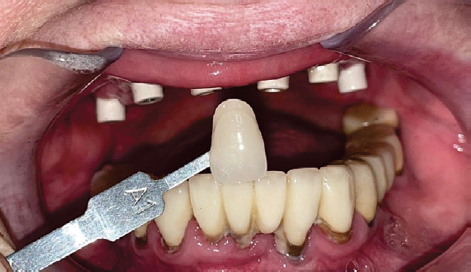

Через полгода после установки дентальных имплантатов хирургом стоматологом установлены мультиюнит абатменты (рис. 6, 7) и поставлены защитные колпачки (рис. 8).

Рис. 6. Проверка угла мультиюнит абатментов

Fig. 6. Angle of the abutments

Рис. 7. Фотография мультиюнит абатментов через 2 нед после установки

Fig. 7. Multiunit abutments 2 weeks after insertion

Рис. 8. Установлены защитные колпачки на мультиюнит абатменты, определен цвет будущей временной реставрации

Fig. 8. Protective caps are placed on the multiunit abutments, and the color of the future provisional restoration is determined